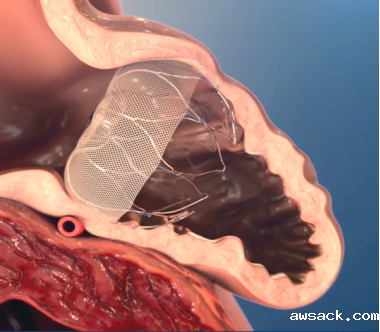

1月19下午,邵江介入团队在全麻下行经股静脉左心耳封堵术,仅用一个多小时就便成功植入WATCHMAN封堵器,经造影和食道超声证实,左心耳封堵完全,封堵器位置良好、固定。张老伯苏醒后转入CCU观察,病情稳定,恢复良好,未出现不良并发症。术后不到24小时转至普通病房能下床活动,而且不到48小时顺利出院。

据了解,房颤是中老年人常见的心律失常疾病,随着年龄的增长,房颤的发生率不断增加。房颤的危害之一就是卒中,房颤患者的中风风险是正常人的5倍。研究数据显示,非瓣膜性房颤患者大部分脑卒中是由于血栓栓塞,而超过90%的血栓来源于左心耳。左心耳内的血栓一旦脱落,随着血流方向进入大脑,就会引起脑卒中。因此房颤的首要治疗目标是预防脑卒中。左心耳封堵术的顺利开展标志着我院在脑卒中防治方面有了新的突破。